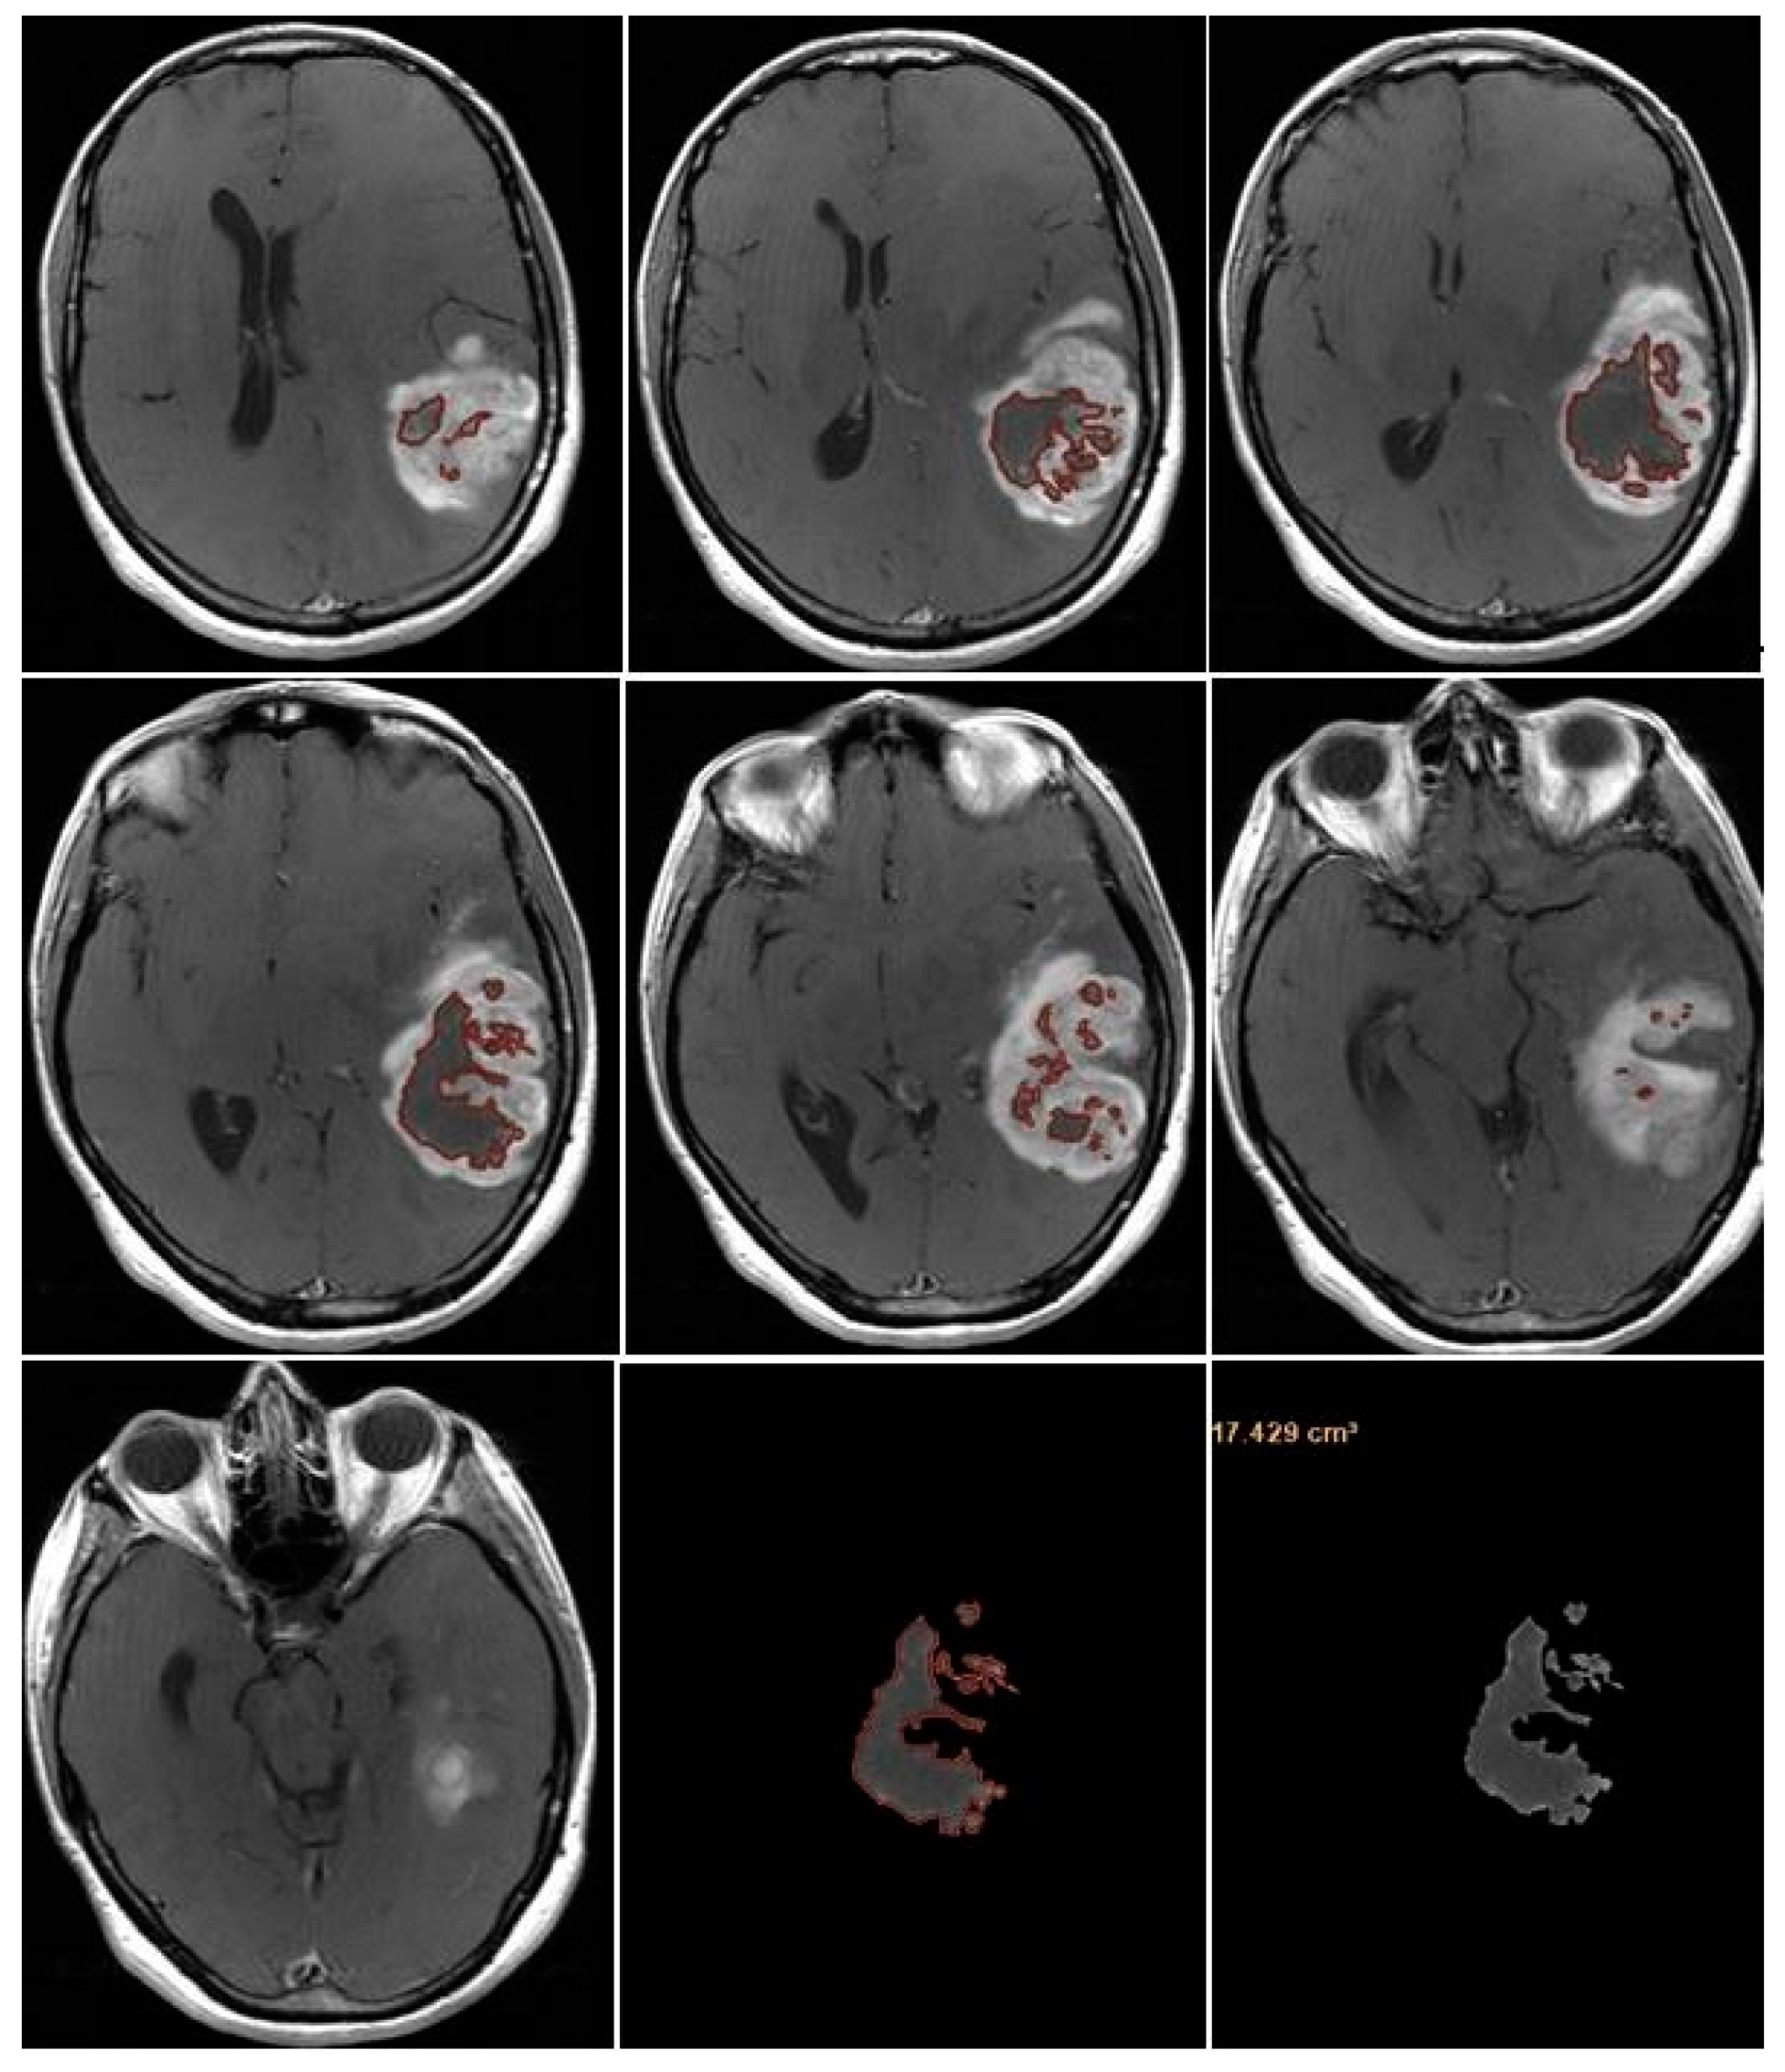

CE-RTV was assessed on 2D axial CE-T1w images (slice thickness: 5 mm.; slice spacing: 5,5-6 mm.), achieved with subtraction imaging technique to minimize errors due to the spontaneous hyperintensity of degradation products of hemoglobin or related to the presence of haemostatic/chemotherapeutic agents in the surgical area. As for CE-PTV, the analysis was performed both manually and semi-automatically [Figure 3 and Figure 4].

NV was evaluated manually on preoperative 2D axial CE-T1w images, including only the necrotic area inside the tumor [Figure 7].

Figure 3. Contrast Enhancement Postoperative Tumor Volume (CE-RTV) manual evaluation.

Preprints 86216 g003

Figure 4. Contrast Enhancement Postoperative Tumor Volume (CE-RTV) semi-automatic evaluation.

Figure 7. Necrosis volume inside the tumor.